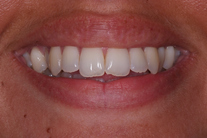

Ung kvinna som tidigare haft tandreglering. Upplever inte att tänderna står i en fin tandbåge. 11 månaders behandling med genomskinliga Invisalignskenor resulterade i ett fint leende.